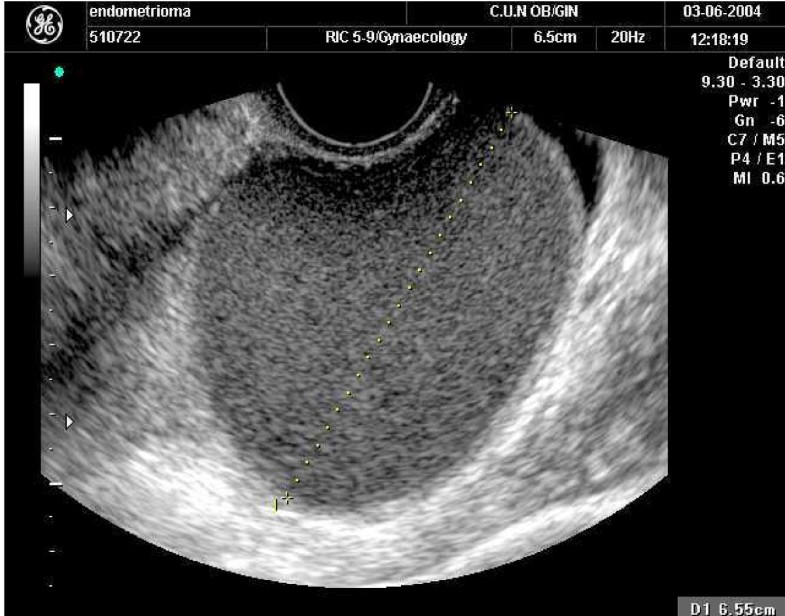

Endometriosis in a postmenopausal woman without previous hormonal

Endometriosis in a postmenopausal woman without previous hormonal Endometriosis Treatment Postmenopausal These include oral contraceptive pills and progestins such as dienogest. Medical management with either the combined oral. The use of gnrh analogues or agonists (such as lupron, synarel,. Women looking to naturally treat their endometriosis after menopause should first turn to their nutrition. Natural treatment for postmenopausal endometriosis. Research shows that having endometriosis symptoms during menopause is more likely if. Endometriosis Treatment Postmenopausal.